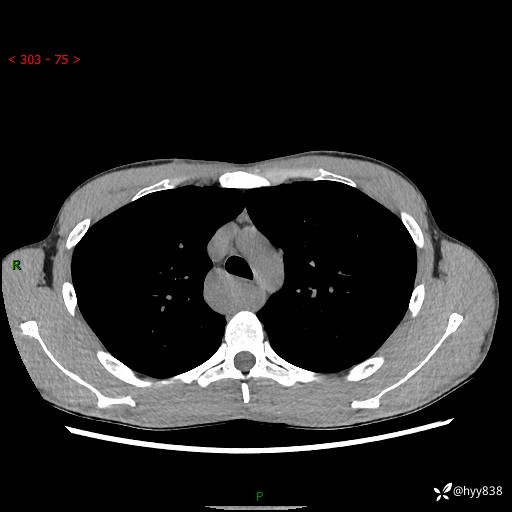

年轻男性,发现后纵隔占位1周余。征象简单,难在定位---结果公布~

现病史:患者于1周前体检行检查发现后纵隔占位,患者平素无明显咳嗽咳痰,无心慌、胸闷、胸痛、呼吸困难、低热、盗汗,无头痛、头晕,无腹痛、腹胀等不适。现患者欲求进一步治疗,遂来我院就诊,以“纵隔占位”收入我科。 患者自起病以来,精神可,睡眠可,饮食可,大小便正常,体重无明显改变。

胸部CT平扫+增强